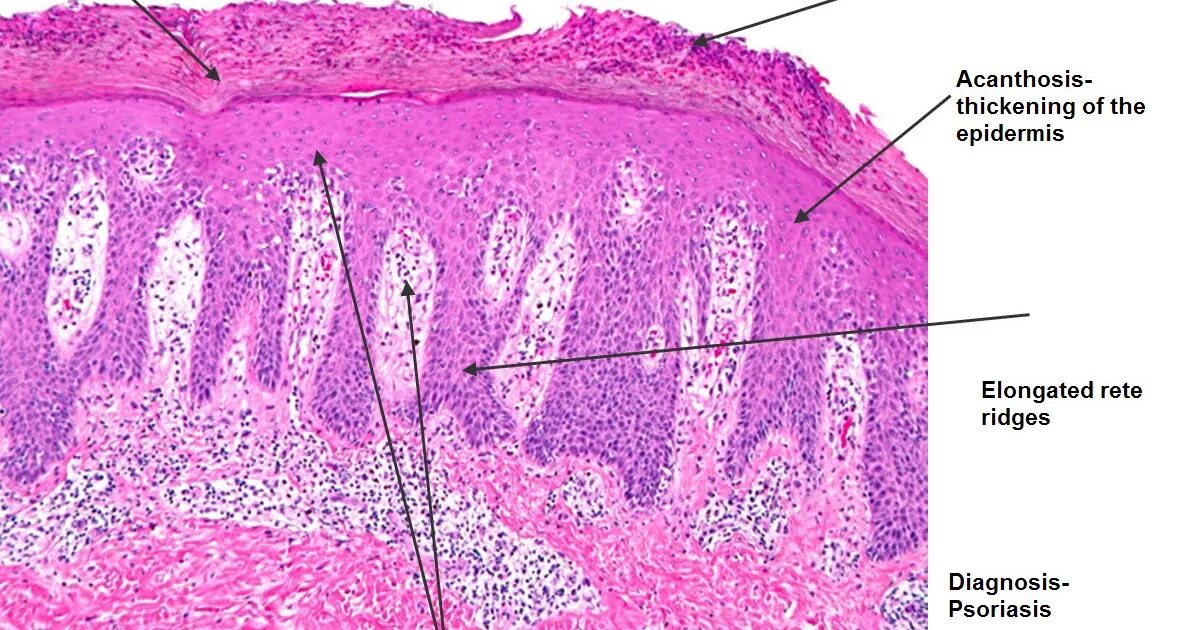

Гистология ростов на дону